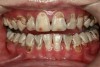

There is no consensus on the frequency of application, and 38% SDF has been used annually or biannually on clinical trials in children23,31,33,34 and in elderly.30,35 Yee and his co-worker found one-off application of 12% SDF was ineffective in arresting caries in children.31 The present authors applied 38% SDF weekly for 3 weeks to speed up the process of caries arrest and for treatment of rampant caries.36 One of the present authors’ case reports demonstrated that three weekly applications of 38% SDF can arrest rampant caries and relieve pain from hypersensitivity on a teenager. The SDF-treated caries were found arrested, and they turned coal black in appearance (Figure 9).

Fig 9. Use of 38% SDF to arrest rampant caries in a young teenager. Fig 8: Pre-treatment intraoral frontal view of rampant caries. Fig 9: Frontal view of arrested caries after consecutive application of SDF for 3 weeks. (images from Chu, et al, 201436 [reprinted with approval])

Figure 9